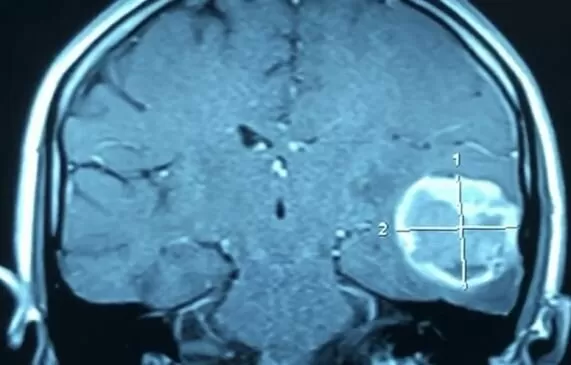

Глиобластома – злокачественная опухоль мозга, которая образуется из глиальной ткани головного мозга. Для глиобласта характерен агрессивный характер (быстрый рост опухоли, инвазивный рост) и склонность к рецидивированию. Средняя продолжительность жизни с момента установления диагноза составляет 12-18 месяцев.

В начале развития заболевания глиобластомы вызывают неспецифические симптомы, такие как головные боли, утомляемость. Согласно увеличению размера глиобластомы появляется неврологическая симптоматика: впервые обнаружены эпилептические приступы, очаговая неврологическая симптоматика (расстройства ощущений, зрения, слуха, парезы), а также нейрокогнитивные расстройства, связанные с увеличением внутричерепного давления.

У пациентов с глиобластомами используются все виды противоопухолевого лечения: оперативное, лучевое, химиотерапевтическое. Учитывая наличие компрессионно-дислокационного синдрома, вызываемого глиобластомой, оперативное нейрохирургическое лечение всегда стоит на первом месте. Лучшие показатели выживаемости наблюдаются у пациентов в возрасте до 50 лет при лучших показателях соматического здоровья и возможности радикального удаления глиобластомы.